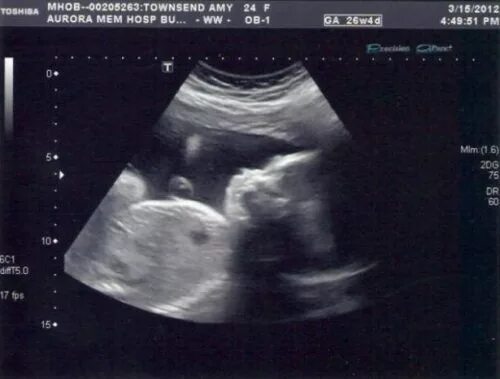

Узи 6 месяцев